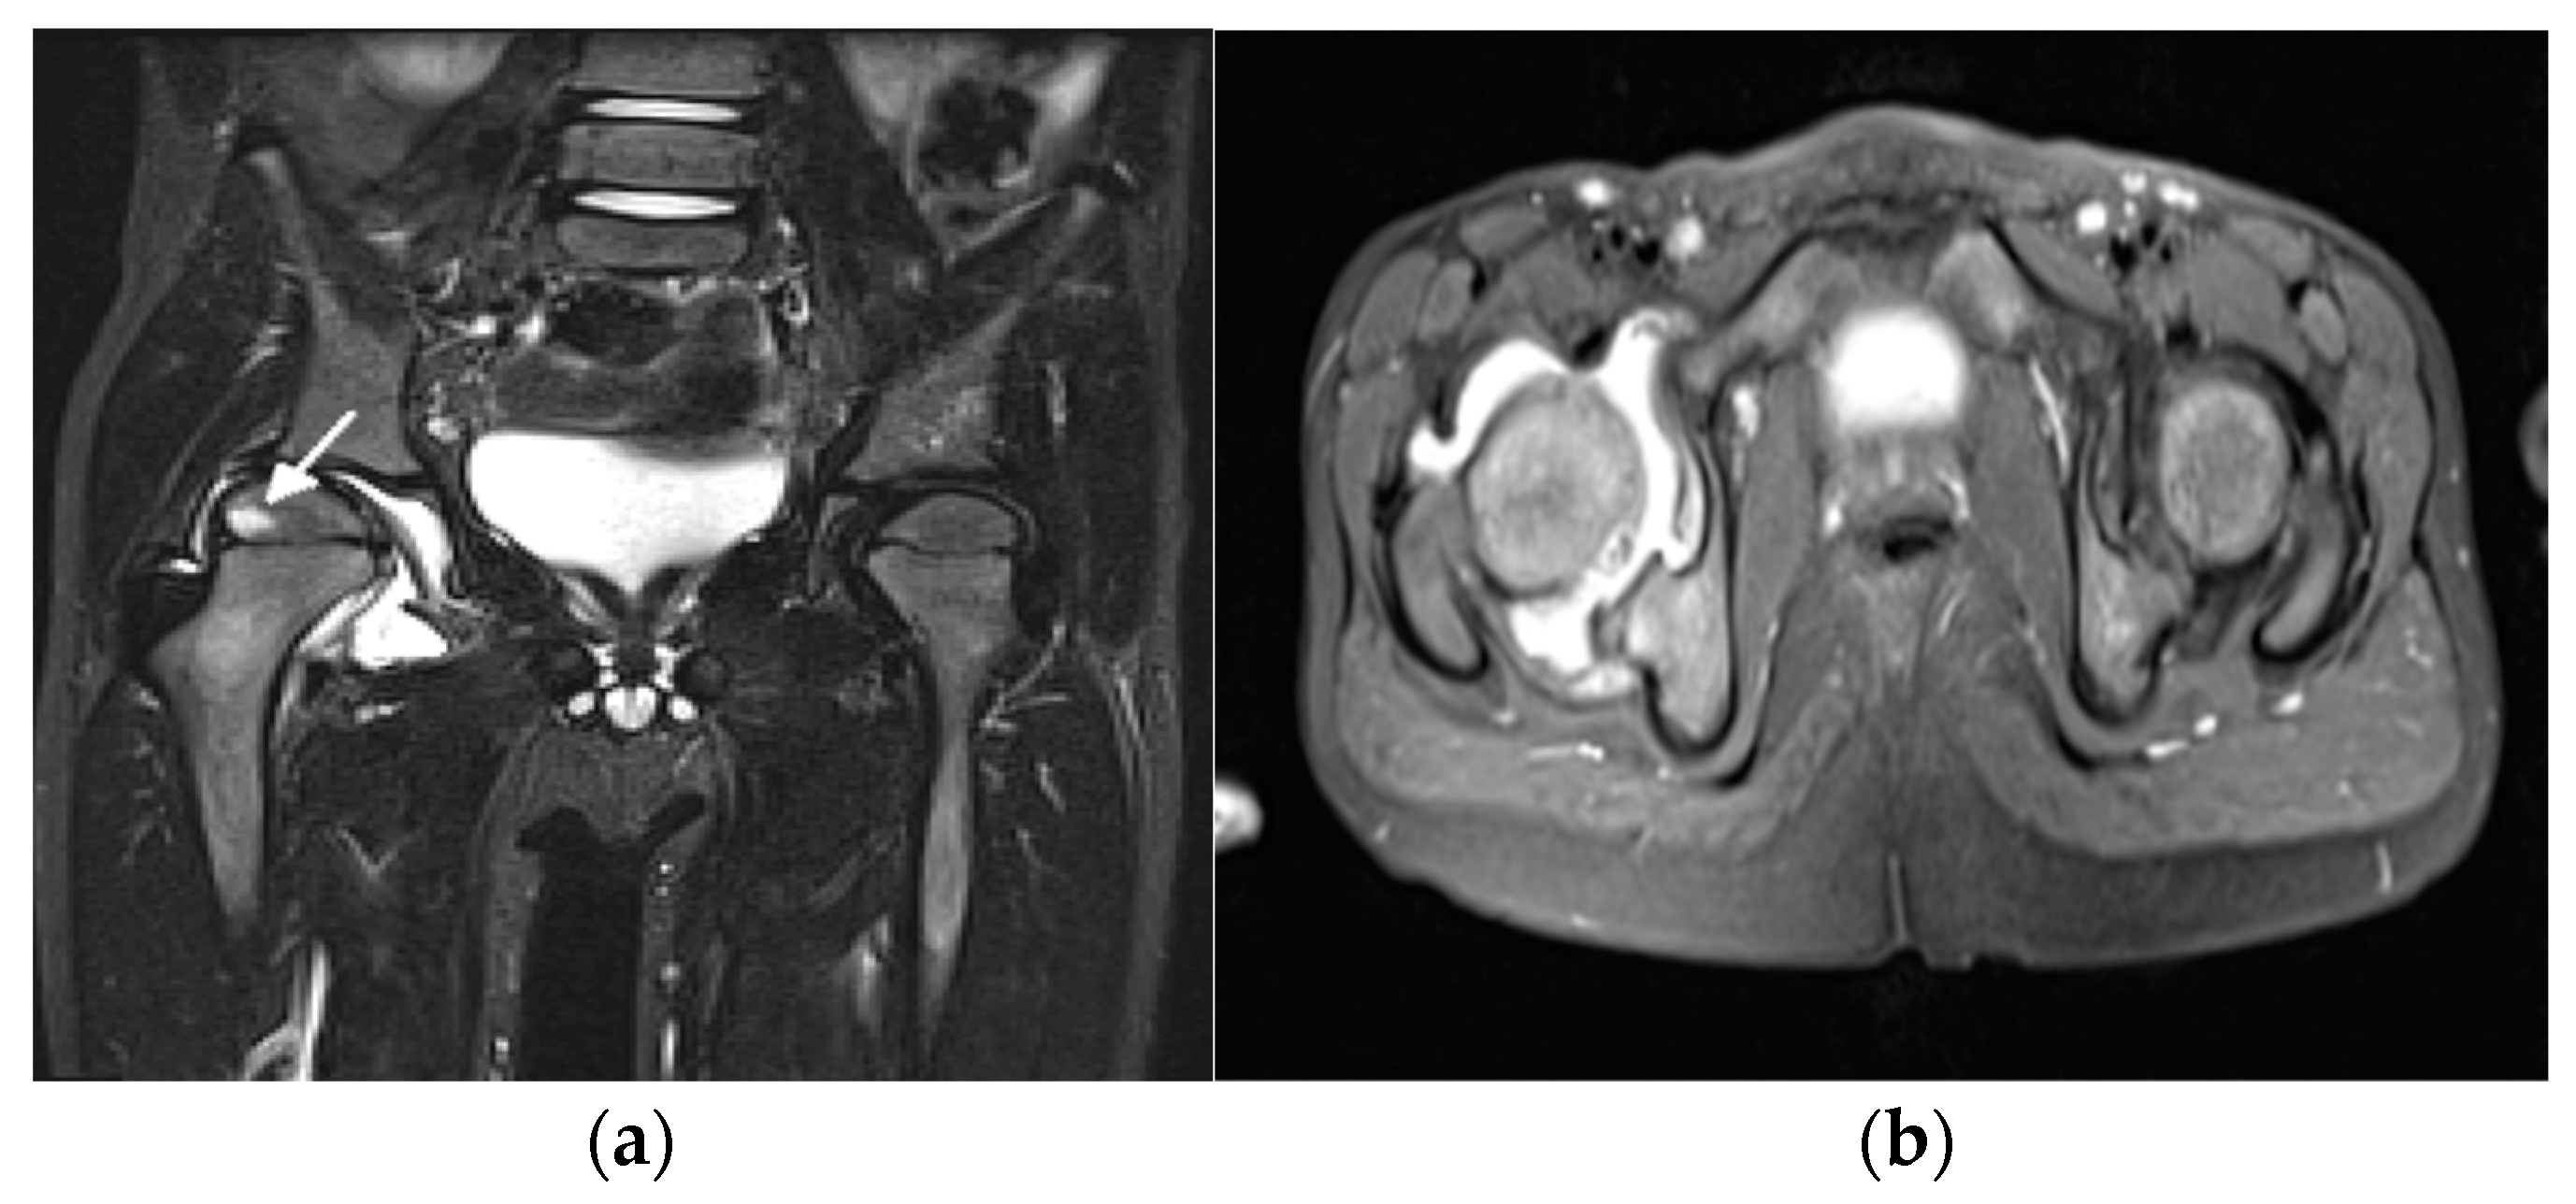

- Ostrowska, M.; Gietka, P.; Mańczak, M.; Michalski, E.; Sudoł-Szopińska, I. MRI Findings in Hip in Juvenile Idiopathic Arthritis. J. Clin. Med. 2021, 10, 5252. [Google Scholar] [CrossRef] [PubMed]

- El-Azeem, M.I.A.; Taha, H.A.; El-Sherif, A.M. Role of MRI in evaluation of hip joint involvement in juvenile idiopathic arthritis. Egypt. Rheumatol. 2012, 34, 75–82. [Google Scholar] [CrossRef][Green Version]

- Argyropoulou, M.; Fanis, S.L.; Xenakis, T.; Efremidis, S.C.; Siamopoulou, A. The role of MRI in the evaluation of hip joint disease in clinical subtypes of juvenile idiopathic arthritis. Br. J. Radiol. 2002, 75, 229–233. [Google Scholar] [CrossRef]

- Murray, J.G.; Ridley, N.T.; Mitchell, N.; Rooney, M. Juvenile chronic arthritis of the hip: Value of contrast-enhanced MR imaging. Clin. Radiol. 1996, 51, 99–102. [Google Scholar] [CrossRef]